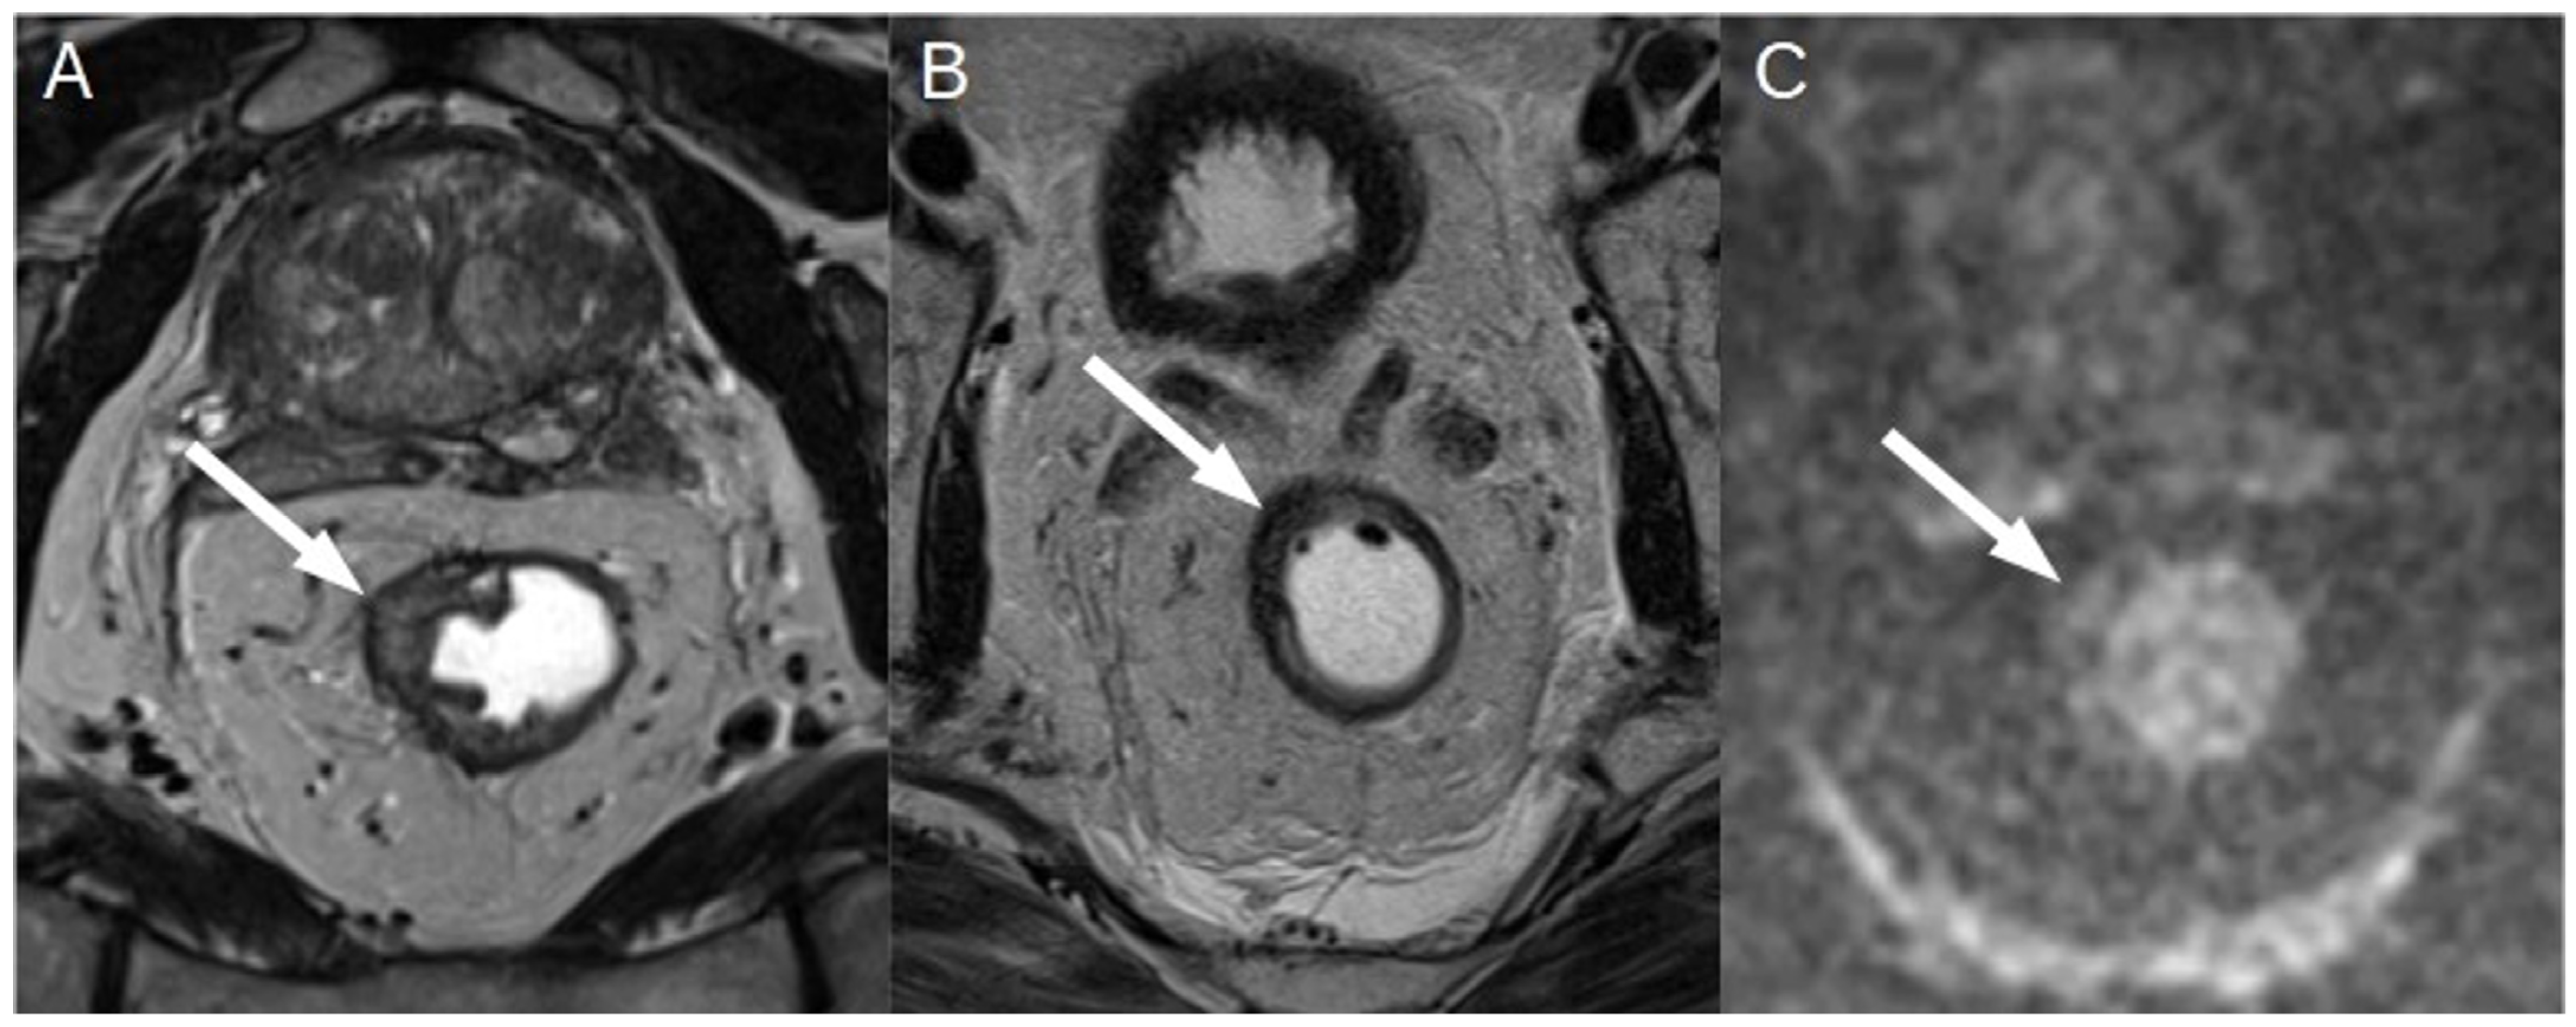

3.1. T Staging

3.2. N Staging

3.3. New Techniques and Applications